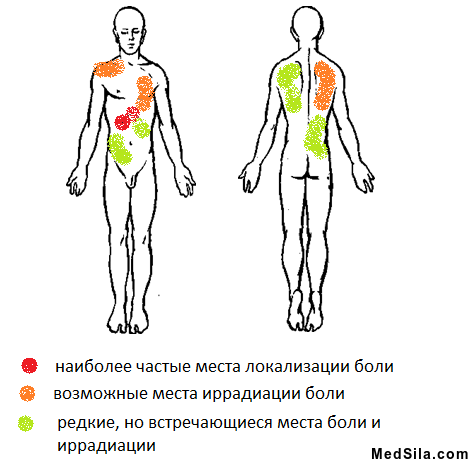

- боли в правом подреберье, иногда под «ложечкой», которые могут отдавать в правое плечо и под правую лопатку, редко в левую половину тела. Боли обычно тупые или тянущие и проходят самостоятельно или при приеме спазмолитиков через несколько часов, реже дней. Обычно они появляются при погрешности в диете: жареное, острое, соленое, копченое, употребление спиртных или газированных напитков; сильных стрессах или после чрезмерной физической нагрузки;

- острая боль в правом подреберье;